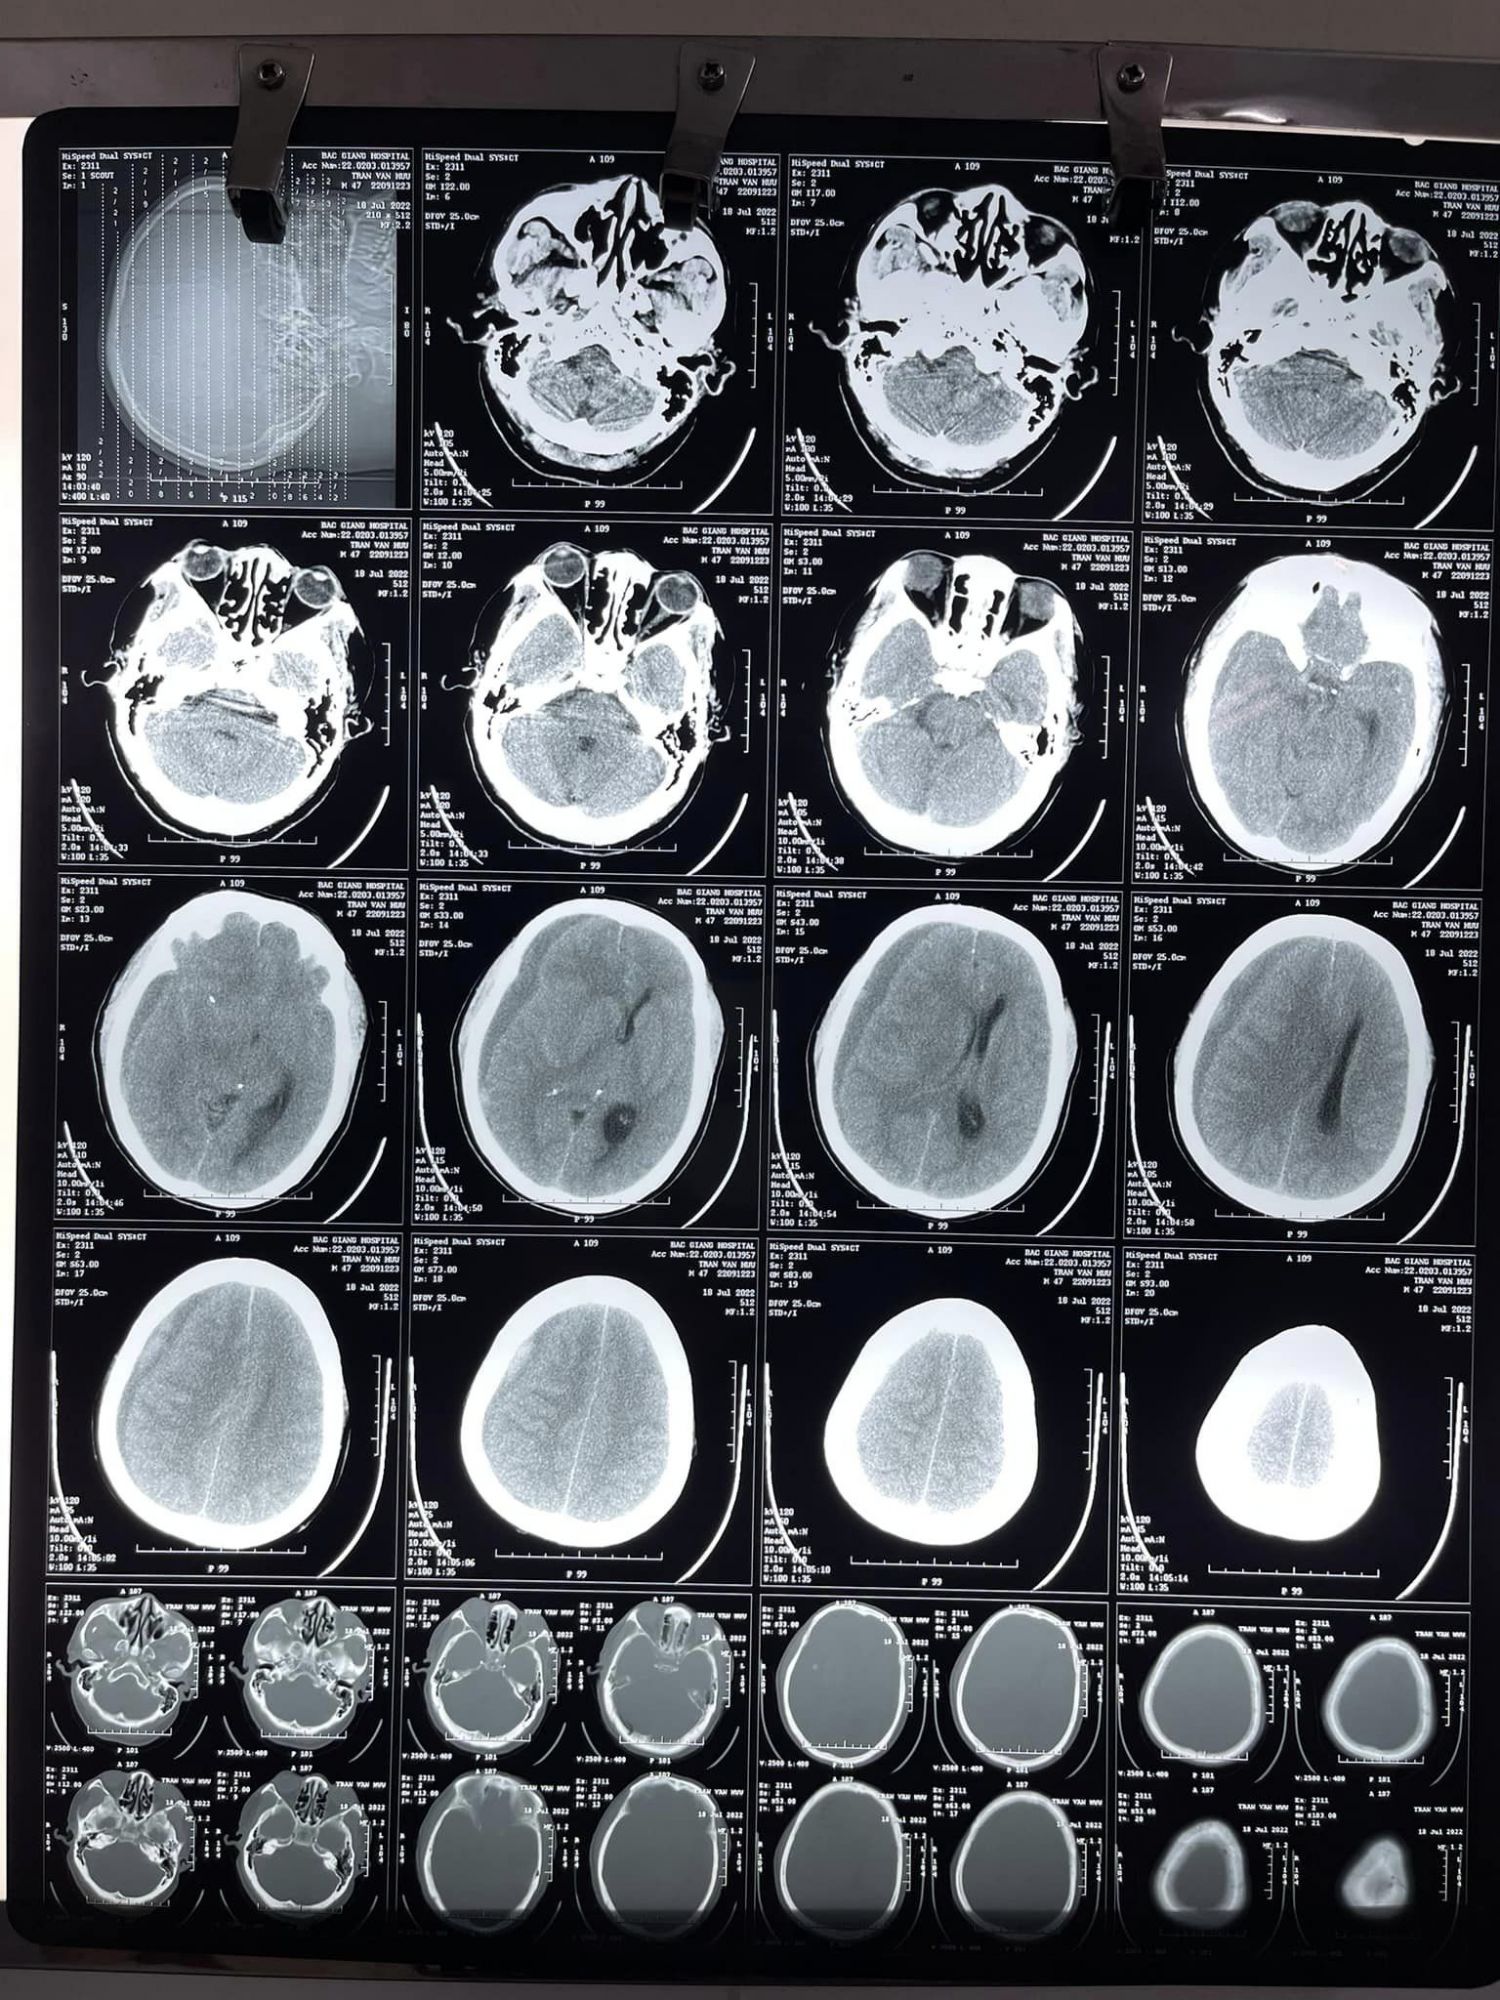

Tại đây, sau khi được bác sĩ thăm khám và làm các cận lâm sàng, ông H được chẩn đoán chấn thương sọ não, tụ máu dưới màng cứng não bán cầu phải trên nền bệnh nhân tăng huyết áp và đã chạy thận nhân tạo chu kỳ 14 năm. Nhận thấy đây là một ca bệnh khó, phức tạp, các bác sĩ đã tổ chức hội chẩn liên chuyên khoa: Ngoại thần kinh, Nội tim mạch, Nội thận TNLM, Hồi sức tích cực- chống độc, Phẫu thuật gây mê – hồi sức và đi đến thống nhất tiếp tục điều trị tích cực cho bệnh nhân. Sau vài ngày điều trị, nhận thấy tình trạng người bệnh tiến triển nặng, khối máu tụ to lên gây ra sự chèn ép lên não và đe dọa tính mạng của người bệnh nếu không được can thiệp kịp thời. Ngay lập tức, một cuộc hội chẩn mới giữa các chuyên khoa liên quan đã diễn ra và nhanh chóng, bệnh nhân có chỉ định phẫu thuật lấy máu tụ dưới màng cứng bán cầu não (P). Kíp mổ gồm Bs.CKII Mạc Hoàng Dương - Trưởng khoa Ngoại thần kinh, mổ chính cùng Ths. Bs Dương Văn Tuyên. Ca mổ gặp khó khăn khi người bệnh có nguy cơ rối loạn đông máu, diện đông máu rộng, yêu cầu người phẫu thuật viên phải thao tác nhanh, chính xác, khéo léo không để chạm vào mạch máu ở vỏ não. Sau 2 giờ đồng hồ, bằng kinh nghiệm, đôi bàn tay khéo léo và sự tập trung cao độ, kíp mổ đã cố gắng lấy tối đa máu tụ trong màng não, cứu sống người bệnh. Chỉ 1 tuần sau mổ, tình trạng người bệnh tốt lên nhanh chóng, vết mổ khô, liền tốt, kết quả chụp CT scaner sọ não kiểm tra sau mổ tốt. Sau 10 ngày phẫu thuật, bệnh nhân đã ổn định, trở lại sinh hoạt bình thường, được các bác sĩ cho xuất viện về nhà và tái khám theo hẹn.